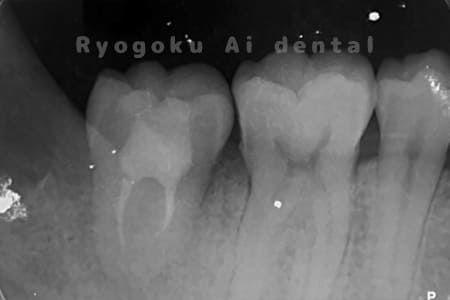

他院で右下の根の治療を行い、セラミックを被せる説明をされていたが、根の治療が終わらないため転院された患者さんです。隣の親知らずの抜歯の必要性と、根の治療を行なっている歯牙の予後が悪いため、移植治療を提案し、右下の親知らずの抜歯と同時に、右下の奥歯(7番)への移植治療を行いました。被せ物を行う必要もなく、順調に経過してます。

<リスク・副作用>

治療後、痛みや違和感、出血、腫れなどが出る事があります。喫煙者、糖尿病などの方の場合、歯が生着しない場合があります。